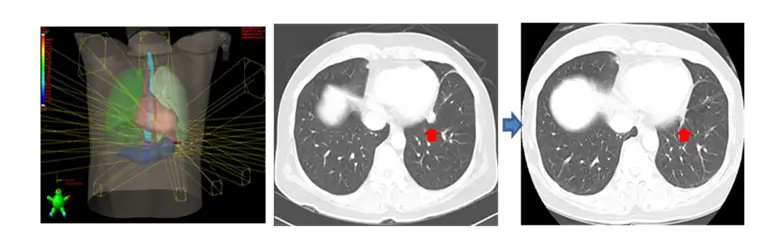

호흡동기 방사선치료 (Respiratory-Gated Radiation Therapy)

호흡주기 맞춤형 4차원 CT 영상을 이용하여 치료 계획을 만들고 치료에 응용하는 호흡동기방사선치료 (Respiratory-gated Radiation Therapy)를 시행하고 있습니다. 방사선치료 중 환자는 평소와 같이 편안하게 호흡을 하고 있으면, 영상장치를 이용하여 종양이 가장 적게 움직이는 호흡주기에만 선택적으로 방사선을 치료하는 방법입니다.

체부 정위적 방사선치료 (SBRT; Stererotactic Body Radiation Therapy)